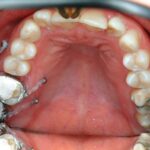

덧니교정

치아가 삐뚤빼뚤 불규칙하게 나거나 겹쳐난 경우에는 심미적으로 좋지 않아

환자의 자존감을 떨어뜨릴 뿐 아니라 잇솔질 관리가 되지 않아 충치나 잇몸질환에 이환될 가능 성이 높으므로 반드시 교정치료가 필요합니다.